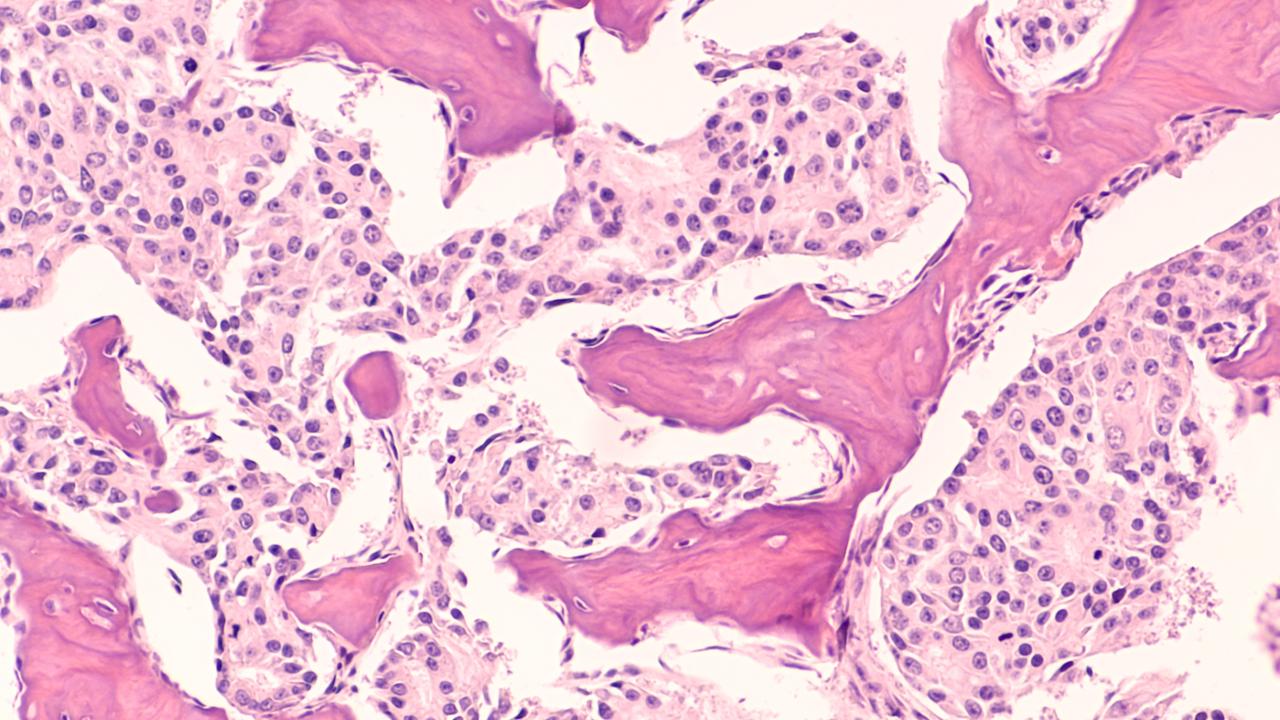

Photomicrograph of bone biopsy showing metastasis of prostatic adenocarcinoma within the marrow space.

Metastatic prostate cancer: photomicrograph of bone biopsy showing metastasis of prostatic adenocarcinoma within the marrow space.